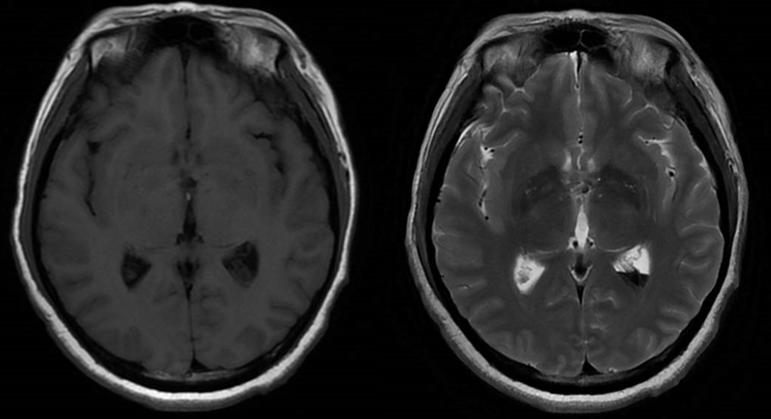

诊治过程:结合患者临床表现及影像学表现,初步诊断考虑为三脑室后部胶质瘤合并梗阻性脑积水可能性大,术前制定的手术方案为经胼胝体穹隆间入路三脑室后部肿瘤切除术+脑室镜辅助下三脑室底造瘘术,该手术方式既可切除肿瘤获取病理,同时可行三脑室底造瘘解决脑积水症状。术中采用冠状缝前额部弧形切口,术中沿纵裂牵开双侧大脑半球,探及胼胝体,沿中线切开胼胝体,分离双侧透明隔,暴露双侧穹隆,严格沿中线分离双侧穹隆,保护两侧穹隆的完整,避免引起术后的记忆力障碍,牵拉开双侧穹隆,进入中间帆,显露并分离双侧大脑内静脉继续向下,经脉络膜隔进入三脑室,完全显露肿瘤组织,肿瘤组织呈灰红色,血供极其丰富,与中脑黏连紧密,仔细分离,分块全切肿瘤,双侧大脑内静脉及中脑保护良好,中脑导水管通畅。肿瘤完全切除后,考虑到术后局部粘连、肿瘤复发等因素可能导致脑积水不缓解,置入脑室镜向前方探查,小心切开中间块,在双侧乳头体与漏斗隐窝之间,行三脑室底部造瘘并打开Liliequist膜及基底动脉旁蛛网膜,确认漏口通畅且与脚间池相通。患者术后恢复过程平稳,颅脑MRI提示肿瘤切除满意,脑积水缓解。术后病理结果示:中枢神经细胞瘤(2级)。术后予以放疗GTV 5400cGy、PTV 5040cGy,28f。现术后已3年,复查未见肿瘤复发,脑积水已完全缓解。

中枢神经细胞瘤 (central neurocytoma,CNC)是一种少见的神经来源的脑室内肿瘤,属 WHO 分级2级。 CNC多生长于脑室,以侧脑室最好发,多数肿瘤位于室间孔附近、侧脑室透明隔或侧脑室壁。少数可发生于胼胝体、穹窿、尾状核头部、丘脑和小脑,脑室外也有发生,但极为罕见。本例肿瘤位于三脑室后部,也比较少见。中枢神经细胞瘤的治疗以手术为主,若能手术全切除,可获得良好的治疗效果,若手术不能全切,术后辅以局部放疗能明显增加局部控制率,亦有研究报道伽玛刀治疗能明显增加残留肿瘤的控制率。